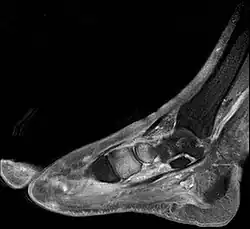

Charcot-Fuß Grad 0, aktives Stadium. Klinisches Bild: geschwollener Fuß

Charcot-Fuß Grad 0, aktives Stadium. Magnetresonanztomographie : Knochenmarködem im Bereich der Fußwurzelknochen